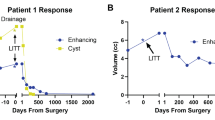

Three patients underwent 5 LITT procedures for pLGG, 2 boys, and a girl. All procedures were performed under general anesthesia. Out of the three patients with LGG (Table 1), in one patient, LITT was done as the first surgical option (low-grade left cingulate glial tumor), while in two patients, LITT was done as an additional surgery after a previous open resection (recurrent right thalamo-peduncular pilocytic astrocytoma, and recurrent right parietal oligodendroglioma). In all 5 procedures, a single LITT trajectory was performed with the 10-mm Visualase fiber. There were no morbidity or complications in our cohort, and no wound complications were observed. The follow-up time ranged between 20 and 40 months, (median 30 months, average 28.6 months). Two of the patients with LGG required a second LITT procedure. One of them was planned for a staged procedure (case #2), and the second patient for a distant enlarging lesion (case #3). Volumetric analysis of the tumor (using the Brainlab neurosurgical navigation software; Munich, Germany), before LITT and later and at different time points (Table 2), showed an initial increase in volume immediately post-operatively, then gradually decreasing in size, consistent with the existing literature [6].

On follow-up imaging, lesions’ volume usually transiently increases in the first 2–4 weeks after the procedure and then gradually decreases, returning to pre-ablation volumes around 3 months after the procedure [25]. This pseudo-progression effect is thought to be mediated by post-ablation inflammatory processes due to thermal necrosis, which, like other ischemic processes, leads to increased vascular permeability and, consequently, increased contrast enhancement [26]. Lesions continue to decrease in volume over time, but it is not uncommon for a small residual enhancing lesion to remain even 6–12 months after the ablation (Fig. 1F, G), without evidence of regrowth. This pseudo-progression might be challenging to differentiate from tumor recurrence and requires serial imaging surveillance.